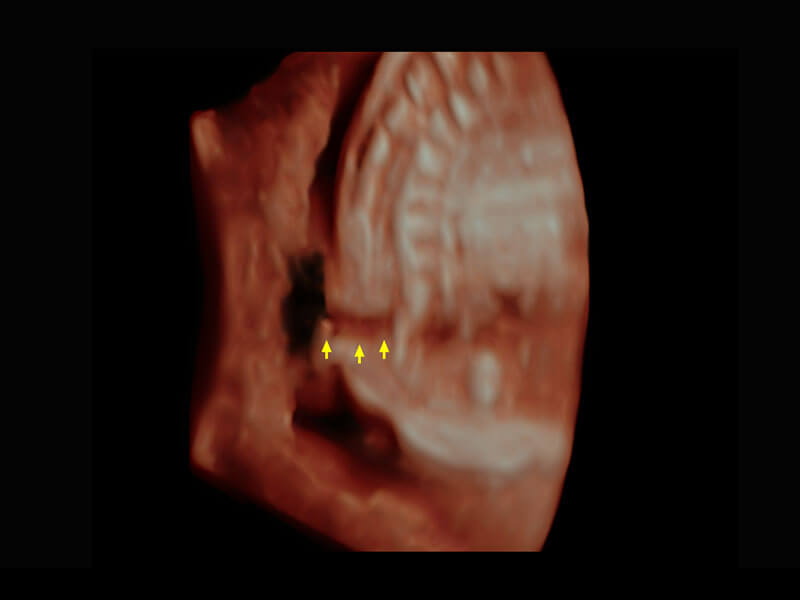

腔内三维-宫内节育器

P60搭载一系列胎儿心脏成像技术,实现精细的胎儿心脏评估。

右室双出口

胎心容积成像